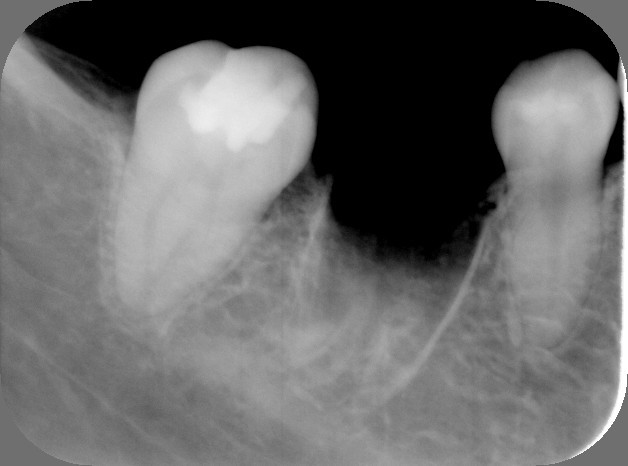

4.移植後3ケ月、骨が出来はじめています。